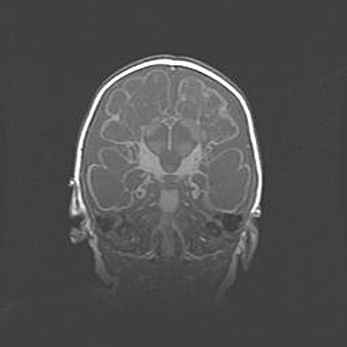

Сообщающаяся гидроцефалия. Кистозная энцефаломаляция головного мозга.

Возраст: 3 месяца 4 дня

Вес: 3100 г

Пол: женский

Окружность головы: 34 см

Срок гестации: 31 неделя

Кистозная энцефаломаляция головного мозга - одна из форм поражения головного мозга в детском возрасте. Характеризуется возникновением множественных и распространённых кист в коре, белом веществе и подкорковых образованиях головного мозга у плодов, новорождённых и детей раннего возраста. Развитие кистозной энцефаломаляции связано с внутриутробной асфиксией и гипотонией, родовой травмой, тромбозом синусов, пороками развития сосудов, инфекциями, сепсисом и другими причинами. Наиболее значимые инфекционные агенты: вирусы простого герпеса, цитомегалии, краснухи, токсоплазмы, энтеробактерии, золотистый стафилококк и другие.